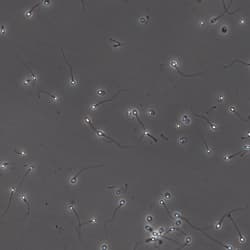

Motility

Tracks, velocities, classification

Counts and % counts: total count, motile, progressive motile, rapid/medium/slow/static classification. Mean velocities: VAP, VCL, VSL, and related metrics (per manufacturer listing). Track overlay for movement visualization. Dose calculation. Read from image sequences in different formats (bmp, tiff, jpeg, etc.). Generate comprehensive statistics for one or several fields; transfer results to Microsoft Excel; custom report generator with results and images; slow-motion playback of stored sequences for behavioral studies.